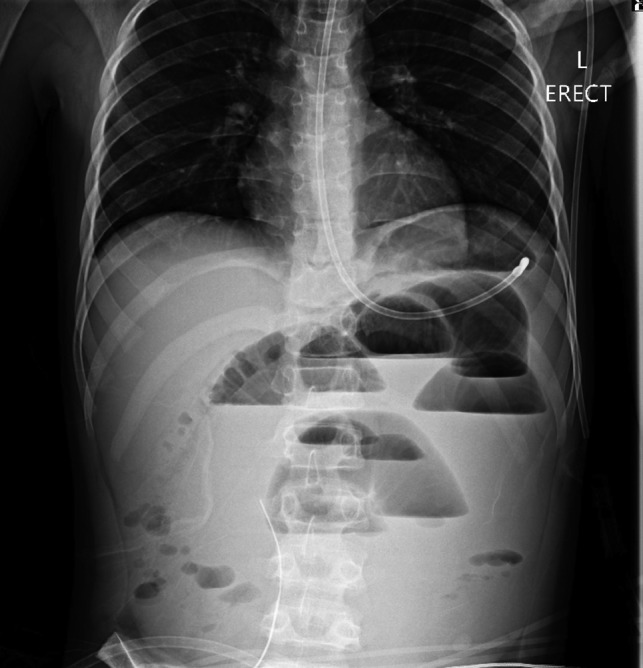

Figure 1:

Erect chest radiograph on postoperative day 2 suggestive of small bowel ileus.